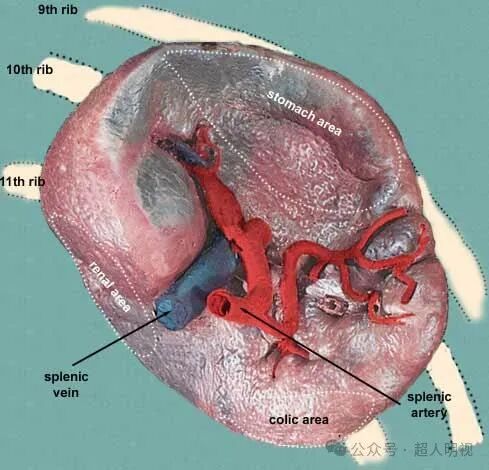

脾大是肝不好?肝硬化与脾肿大有相关性,有哪些症状?做什么检查[s0]高度脾肿大图[s1]轻度脂肪肝引起的脾肿大需要治疗吗[s2]脾大的原因和危害是什么又该如何治疗呢[s3]一.什么是脾脏肿大? 当出现脾大时,一定要高度警惕!下面就一起来看下吧。[s4]出现脾脏肿大就一定是肝硬化了吗?[s5]脾肿大 全网资源[s6]脾肿大一定要切除脾脏吗?[s7]小症状大学问:大牛直播讲解「肝脾肿大」的鉴别诊断与治疗[s8]术后病理结果:淤血性脾肿大伴出血性梗死.[s9]查看:脾脏肿大还能恢复正常吗?[s10]脾脏肿大,发紫图片为检测到感染14天后的猪.[s11]图片[s12]脾大的原因和危害,如何治疗[s13](正常脾脏与肿大脾脏对比)影像学检查:若触诊脾肿大,则需要进一步做[s14]脾肿大 全网资源[s15]白血病有脾脏肿大怎么缩小?[s16]脾肿大[s17]脾肿大 来自搜狐网[s18]脾大[s19]脾肿大 来自网易[s20]脾肿大脾功能亢进能治疗吗[s21]图22.jpg[s22]脾肿大 来自搜狐网[s23]脾大[s24]脾肿大 www.haodf.com[s25]脾肿大 来自搜狐网[s26]脾脏增大[s27]肝脾肿大[s28]脾大的原因和危害[s29]脾肿大,表面有隆起的梗死病灶 皮下少量出血点 膀胱黏膜有血班 血肾表面出血 胃底出血 胃浆膜上有大量[s30]脾肿大切除 - 华夏病理网论坛[s31]脾脏增大[s32]肝脾肿大(再生障碍性贫血)[s33]肝脾肿大,肝功能正常:肝脏疾病?血液系统疾病?[s34]就是脾肿大。事实上,脾脏名堂可多了。请看:一、脾脏解剖 1,血管分布[s35]脾肿大 m.120.net[s36]脾大的症状有哪些表现(脾肿大一定是肝硬化吗?医生:不一定,可能是这7个因素在作怪)[s37]脾肿大(结果已公布)[s38]脾肿大:症状、原因和治疗[s39]